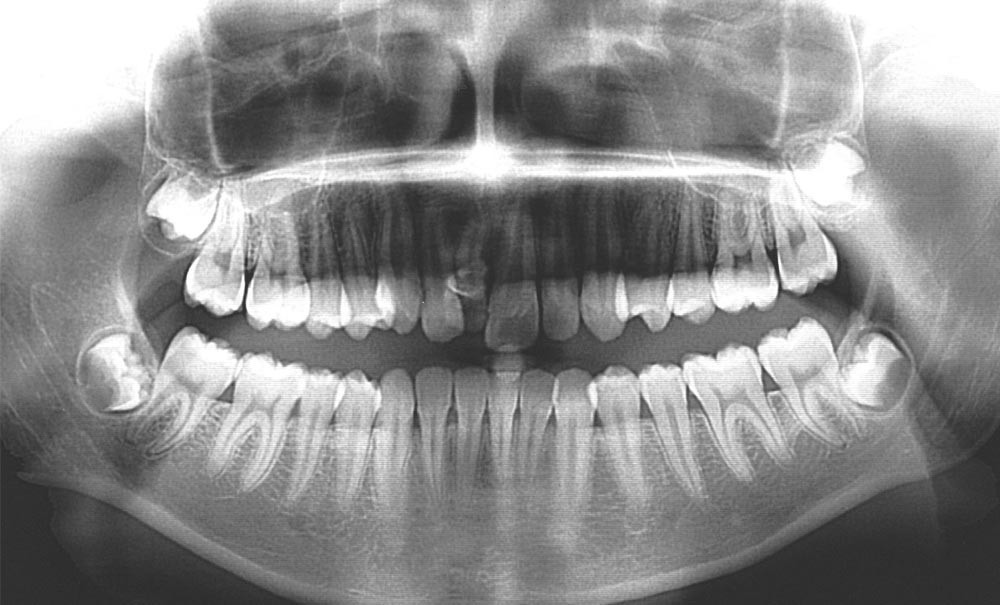

Lors de la phase de finitions, une séance de réévaluation radiographique des axes radiculaires (fig. 3a-b) a permis de corriger les défauts de collage et d’étudier les mouvements squelettiques et dento-squelettiques obtenus.

La comparaison des téléradiographies de profil et l’analyse de la superposition générale sur les structures stables basi-crâniennes (fig. 7) montrent une absence de croissance antéro- postérieure (pas de changement de l’angle ANB) mais une ouverture du sens vertical (angle FMA passant de 24° à 26°) qui reste sans conséquences esthétiques. L’incisive mandibulaire est repositionnée (angle IMPA passant de 99° à 97°). La rotation horaire du plan palatin, de même que l’égression de l’incisive maxillaire, correspond à l’action des tractions intermaxillaires de classe II.